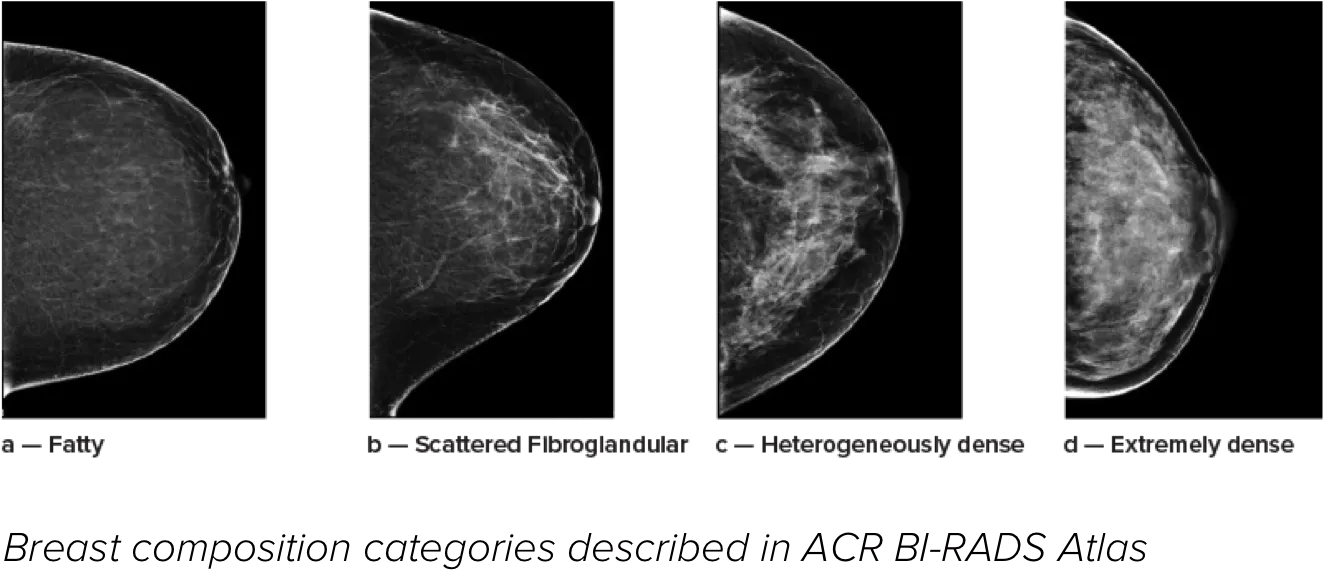

乳腺濃度が高いと、女性の乳がんリスクが高まることが知られています1。したがって、正確でバイアスのない分析が極めて重要です。機械学習を活用する Quantra テクノロジーソフトウェアは、2D™ 画像とトモシンセシス画像の両方を分析して乳腺密度の割合を分類します。米国放射線医学会 (ACR) BI-RADS アトラス第 5 版のガイドラインに従って、乳房を 4 つの乳房組成のカテゴリーに分類します2

リスクカテゴリー8

8. Breast composition categories as described in ACR BI-RADS Atlas.